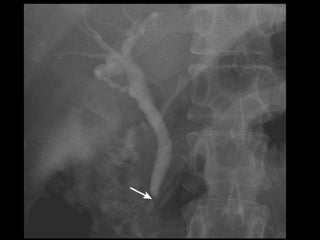

Vias Biliares • Funçãode carrear a bile do fígado para o duodeno. • Intra-hepáticas: 3mm • Bile é produzido continuamente pelo fígado e armazenada na vesícula. • Ductos hepáticos D e E > Ducto hepático comum. (3 – 6 mm) • Ducto Hepático Comum + Ducto Cístico > Ducto Colédoco. ( 8mm)

• 37.

Ducto Colédoco • 5– 15 cm • Finaliza seu percurso no duodeno (lado medial da porção descendente), passando posteriormente à cabeça do pâncreas. • Se liga ao ducto pancreático no meio do caminho formando a ampola hepatopancreatica (Vater), terminando na papila duodenal maior. (Esfincter de Oddi)

Técnicas de Imagem •Rx: – 10 – 15% das colelitiases, estão calcificadas e identificáveis no RX – Pode ser visto também a vesícula em “porcelana.” – Gás pode ser visto dentro das pedra: Sinal de Mercedes-Benz – Colecistografia oral: Ingesta de composto iodado. Atualmente susbstituído pelo US

• 44.

Técnicas de Imagem •US – Método de escolha • Colecintigrafia – Estudo dinâmico. Ver obstruções. • Colangiografia – CPRE: Diagnóstica e Terapêutica. • TC – Menos sensível que US para detectar dilatação.